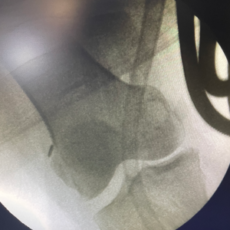

Knee preserving surgery encompasses a range of surgical techniques aimed at treating knee conditions while maintaining the integrity of the natural knee structure. Unlike traditional knee replacement surgery, these procedures focus on repairing and preserving the existing knee joint, thereby reducing recovery time and retaining more of the patient’s original anatomy.

Arthroscopic Surgery: A minimally invasive procedure to diagnose and treat knee problems using a tiny camera and instruments, resulting in less pain and faster recovery.

Cartilage Restoration: Techniques such as microfracture, autologous chondrocyte implantation (ACI), and osteochondral autograft transplantation to repair damaged cartilage and restore joint function.

Osteotomy: A procedure to realign the bones of the knee to shift weight away from damaged areas, providing pain relief and delaying the need for a total knee replacement.

Meniscus Repair: Repairing or replacing the meniscus to restore normal knee function and prevent further joint damage.